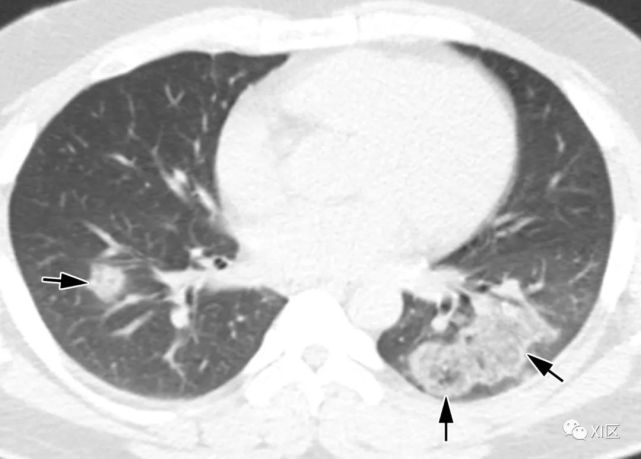

图片

图20 38岁孕妇因甲型流感病毒引致的肺炎,怀孕29周零5天,出现咳嗽及呼吸困难。(上) 最初的胸片显示两肺广泛的斑片状实变(箭),空气支气管征(箭头),特别是在中下肺区。患者进行紧急剖宫产后,对急性呼吸窘迫综合征进行了插管和体外膜充氧。(中) 3周后胸片显示不规则实变强度降低(箭)。(下)在同一天的轴位CT图像显示沿支气管血管束的不规则实变(箭头),弥漫性GGO伴肺小叶间隔增厚(箭头)。对患者进行逆转录聚合酶链反应(RT-PCR)痰、血培养及支气管肺泡灌洗,寻找混合感染的证据。然而,没有证据表明有混合感染。